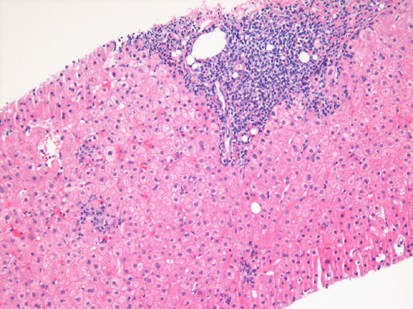

- Inflammation ("Hepatitis"): Infiltration by inflammatory cells.

| C | Flavivirus | Blood/Body Fluids | High | High risk of cirrhosis & HCC; lymphoid aggregates in portal tracts. |

- Acute hepatitis histology shows panlobular inflammation, hepatocyte necrosis, and Councilman bodies (apoptotic hepatocytes).